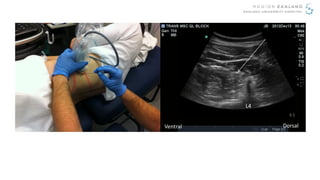

Transmuscular Quadratus Lumborum (TQL) Block

L4

Ventral Dorsal